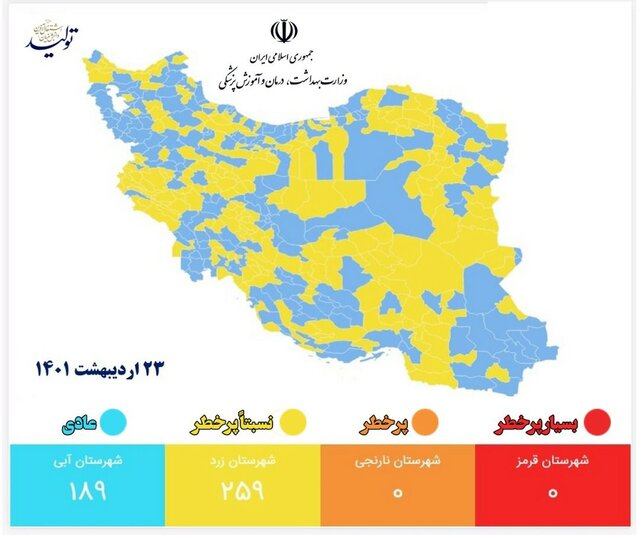

روزهای آرام کرونایی در ایران

کرونا در ایران در شرایط کنترل است؛ بعد از گذراندن روزهای سیاه مرگهای ۵۰۰تایی و [...]